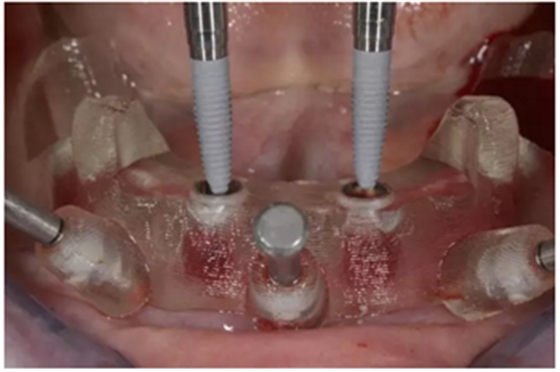

通過固位釘固定上頜NobelGuide外科導(dǎo)板和第一枚已植入的植體和導(dǎo)板基臺。

4枚NobelReplace CC RP4.3植體(11.5mm 軸向植體和13mm 傾斜植體)已植入完成:前牙區(qū)植體上裝配的是導(dǎo)板基臺,后牙傾斜植體上裝配的是內(nèi)錐形連接的引導(dǎo)式持釘器。